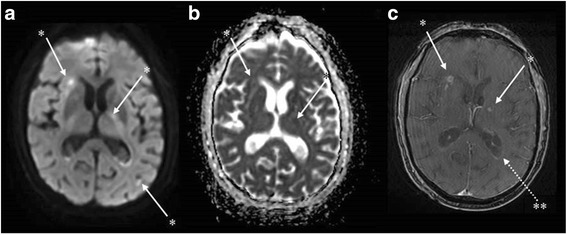

Fig. 2.

Brain magnetic resonance imaging (day 6) showing possible cerebral vasculitis in multiple axial sequences. *Punctiform hyperintensities in diffusion-weighted imaging (a) in several vascular territories with cortical and sub-cortical distribution. These lesions appear with a normal or decreased axial apparent diffusion coefficient value (b) and some are enhanced after gadolinium injection in T1 sequences suggesting a blood-brain barrier disruption (c) and consistent with semi-recent ischemic lesions. **Ependidymal enhancement in T1 with gadolinium enhancement sequences, sign of ventriculitis (c)

The patient’s neurological state progressively improved to regain a vigilant state and was extubated on day 5 of antibiotic therapy. He was discharged to the infectious diseases unit. Nonetheless, he remained confused and somnolent (Glasgow coma score 14/15). Magnetic resonance imaging (MRI) with T2 fluid-attenuated inversion recovery (FLAIR) sequences performed on day 6 revealed the presence of a declivous purulent material inside the lateral ventricles with a moderate dilatation of these structures, not requiring any drainage (fig. 1). This material showed restricted diffusion (decreased apparent diffusion coefficient [ADC] value) and no magnetic susceptibility artefacts on T2* sequences, ruling out the possibility of a blood sediment. It also revealed punctiform hyper intensities in T2 weighted sequences and b1000 diffusion-weighted imaging (DWI) in multiple vascular territories with cortical and deep white matter distribution. These lesions were characterised by a normal or decreased ADC value and some of them were enhanced after gadolinium injection (fig. 2). All of these findings were consistent with semi-recent ischemic strokes.